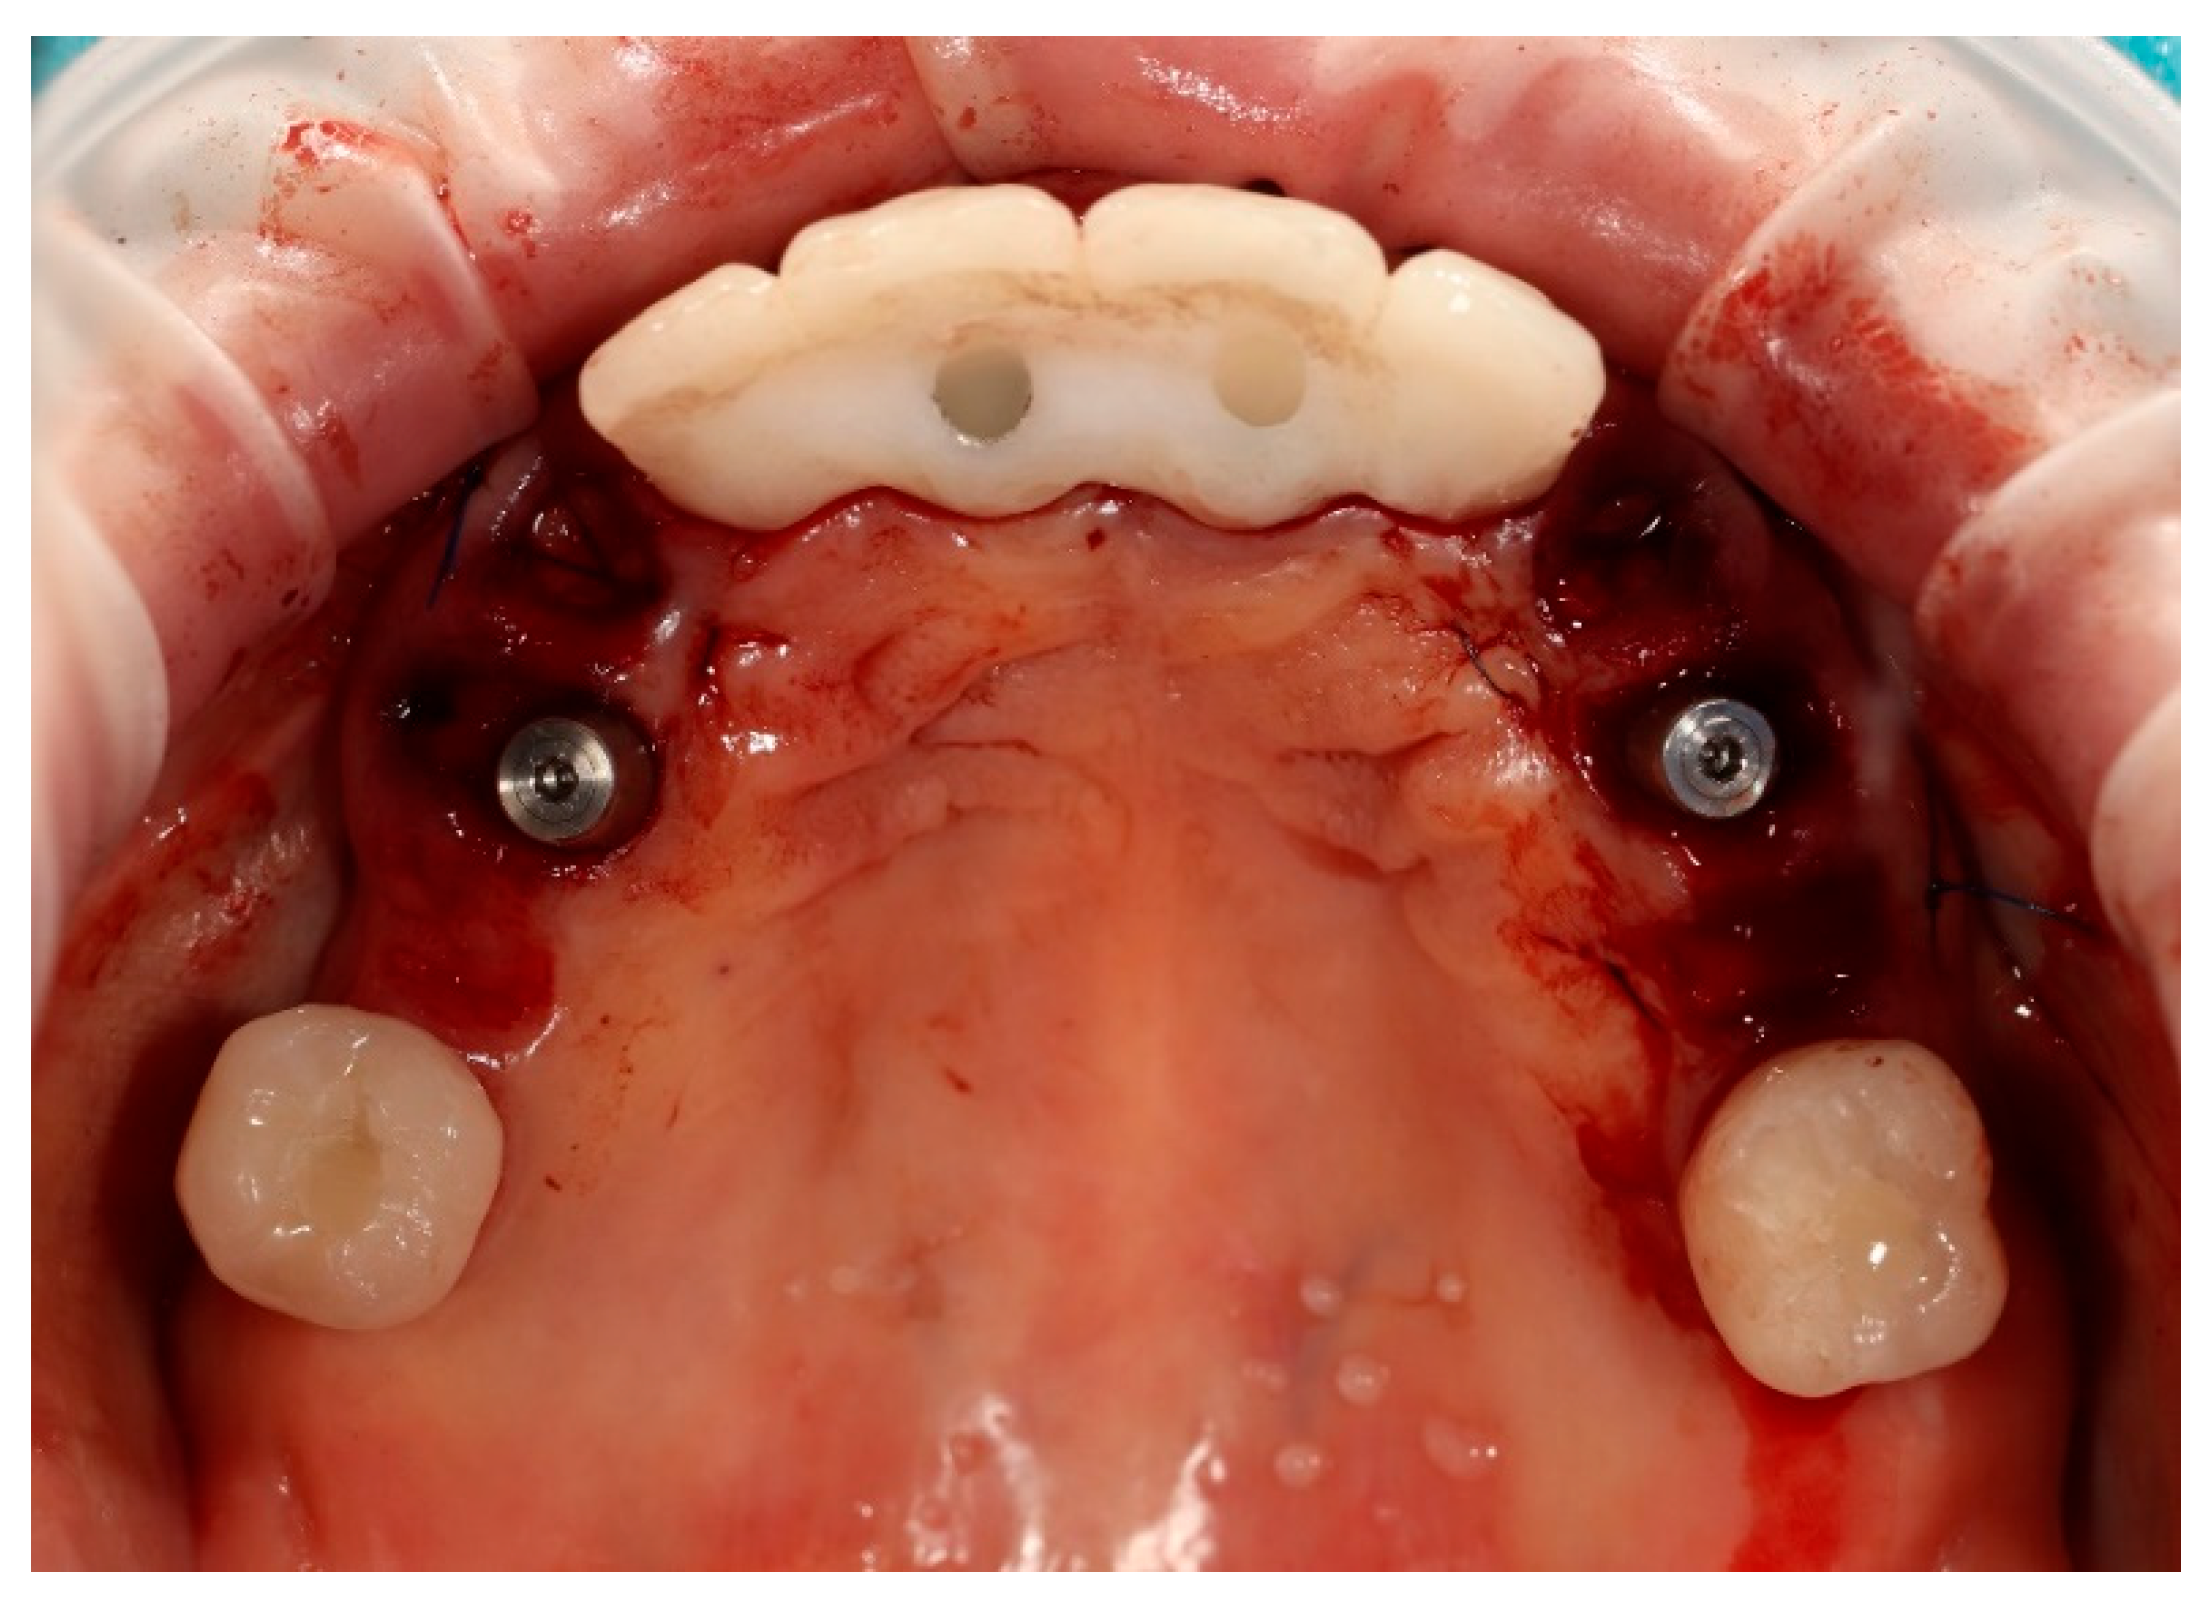

Upon removal of the provisional bridge from the multi-unit abutments, well-conditioned soft tissues were observed, adequately shaped by ovate pontics and corresponding to the requirements of the FP1-type full-arch prosthesis (Figure 13). No signs of inflammation or adverse response were noticed. As highlighted in the literature, provisional restorations are considered crucial for conditioning peri-implant soft tissues, as they help to establish the emergence profile and papillae prior to the definitive prosthesis being fitted [20].

Figure 13. Multi-unit abutments in situ after the removal of the provisional bridge, showing well-healed peri-implant soft tissues contoured by the pontics of the temporary restoration.